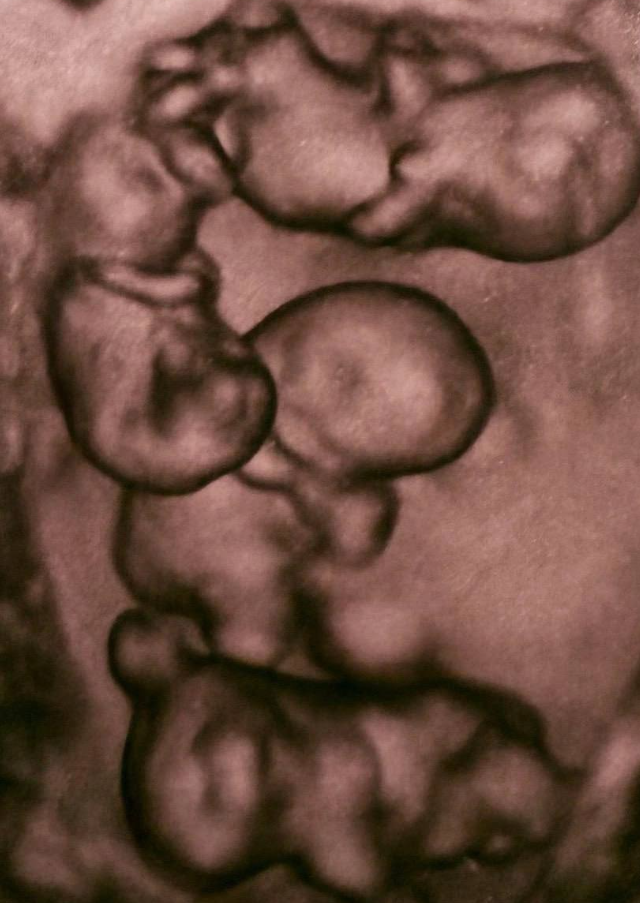

В Санкт-Петербурге произошёл редчайший случай для России — женщина родила однояйцевых четверняшек. Вероятность такого события оценивается примерно как 1 на 15,5 миллиона родов.

На свет появились четыре абсолютно идентичные девочки, сейчас за ними наблюдают врачи. Подобные случаи — настоящая редкость: во всём мире зафиксировано около 15 таких рождений, и чаще всего это именно девочки.